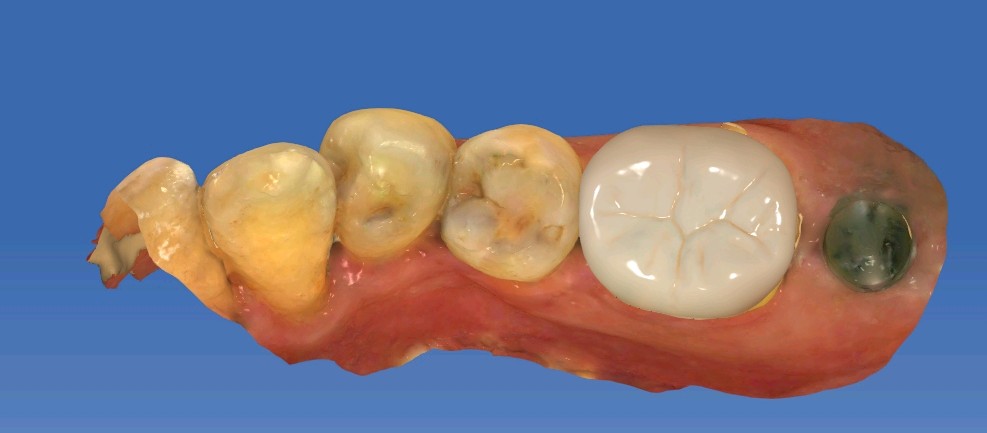

患者男,五十岁,右下后牙咬合不适,前来外院就诊。X线片显示46根尖部有阴影。口内检查发现,颌面大面积树脂充填物,周边有继发性龋坏。探-,叩+,余无不适。治疗计划:根管治疗后高嵌体修复。

补牙在操作过程中很容易受到唾液污染、口腔空间较小等因素影响粘结效果,长期磨耗容易脱落缺损。从而进一步引发继发龋。基牙很容易受损。根管治疗后的牙齿可以选择高嵌体和牙冠修复。这位患者牙体缺损不是较少,所以建议高嵌体修复。先用数字化口扫技术扫描患者口腔内备好的牙体形态,在口外模型上由专业技师制作出来,最后再由医生将嵌体粘固在缺损的牙齿上修复,因此治疗过程一般需要1-2次。更精细,密合度高,修复后牙缝不易塞牙 更好恢复咀嚼功能,窝沟点隙也更加清晰。

术前

术中

术后